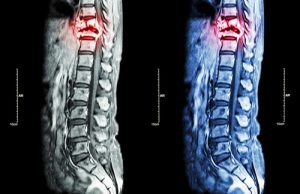

Диагностика эпендимомы в Израиле

Своевременность и точность диагностики – одни из главных залогов успешности терапии. Именно поэтому все исследования в центре СТС выполняются крайне оперативно, с использованием наиболее высокоспецифичных методик. Если же пациент уже прошел диагностику у себя на родине, ему предлагается для начала воспользоваться услугой «Второе мнение». В формате видеоконсультации врач из клиники проанализирует все медицинские документы и составит по ним свое заключение. Если у специалиста возникнут сомнения относительно достоверности поставленного врачами из стран СНГ диагноза, на обследование рекомендуется отправиться непосредственно в Израиль. Это займет всего три-четыре дня, причем первичный прием после видеоконсультации будет бесплатным.

- Магнитно-резонансная томография.